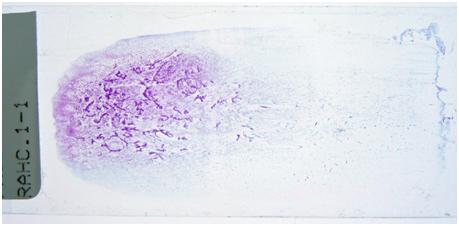

On the top is a glass slide with cells, stained purple so we can see them. Below it is what the cells look like down the microscope, the magnification is 400x what you can see with your eye.